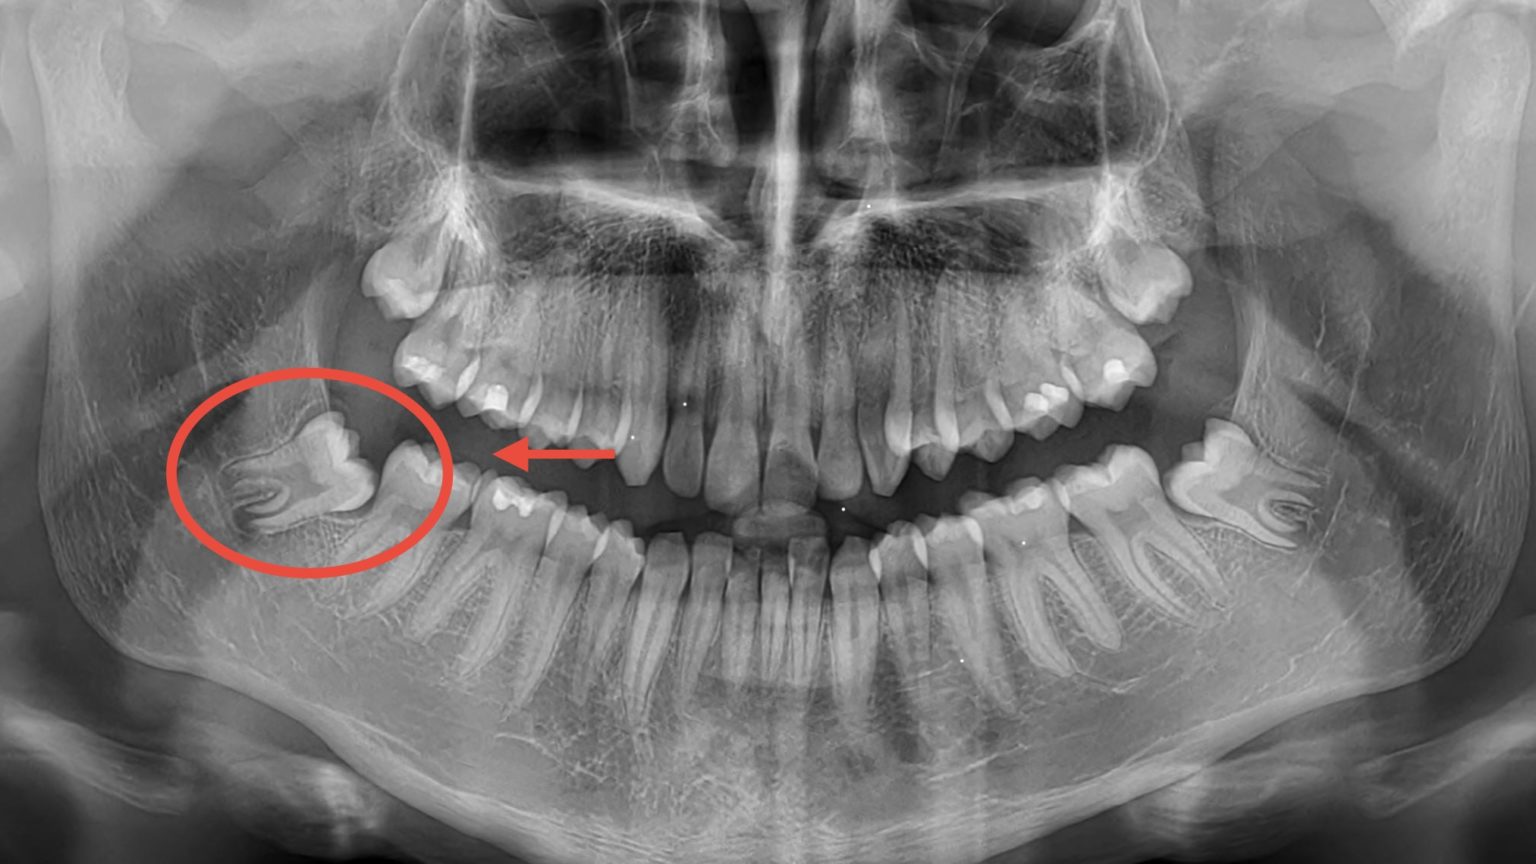

Ma, diciamocelo, i denti del giudizio a volte sono dei veri e propri artisti della complicazione. Magari sono sepolti come un tesoro pirata, magari sono piegati in posizioni che farebbero invidia a un contorsionista circense. In questi casi, l'estrazione diventa un po' più "artistica", e di conseguenza, il prezzo sale. Parliamo di cifre che potrebbero andare dai 200 ai 400 euro, a volte anche qualcosina in più, a seconda della complessità.

E se il vostro dente del giudizio ha deciso di nascondersi come un ninja? Se è completamente incluso nell'osso, magari a malaposta, allora siamo di fronte a un intervento un po' più... "specializzato". Qui entra in gioco il chirurgo orale, un vero e proprio mago della bocca! In questi casi, la tariffa estrazione dente del giudizio può variare considerevolmente. Diciamo che potreste trovarvi di fronte a cifre che vanno dai 300 ai 700 euro, e a volte, per casi davvero ostici e se sono più di uno, potremmo spingerci anche oltre i 1000 euro. Ma non fatevi prendere dal panico! Questo è per i casi più impegnativi, quando il dente è un vero e proprio "intruso" che ha bisogno di essere persuasodalla cavità orale.